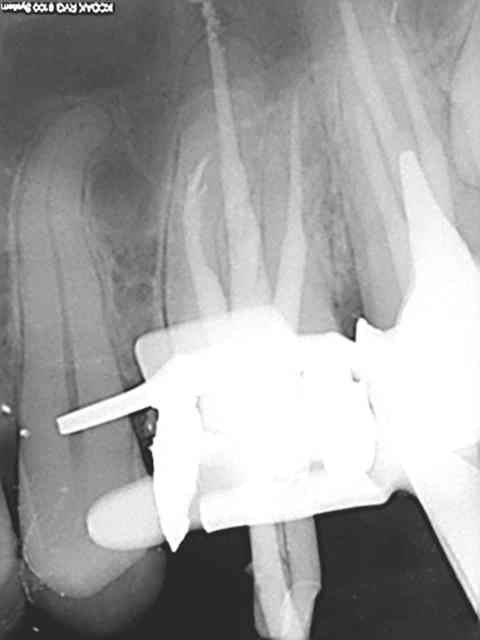

24/10/2013 à 17h06

Cas moins évident mais qui n'a pas non plus posé de problème.

R3 qffody - Eugenol

R1 zrrh3g - Eugenol

R2 qc4kxq - Eugenol